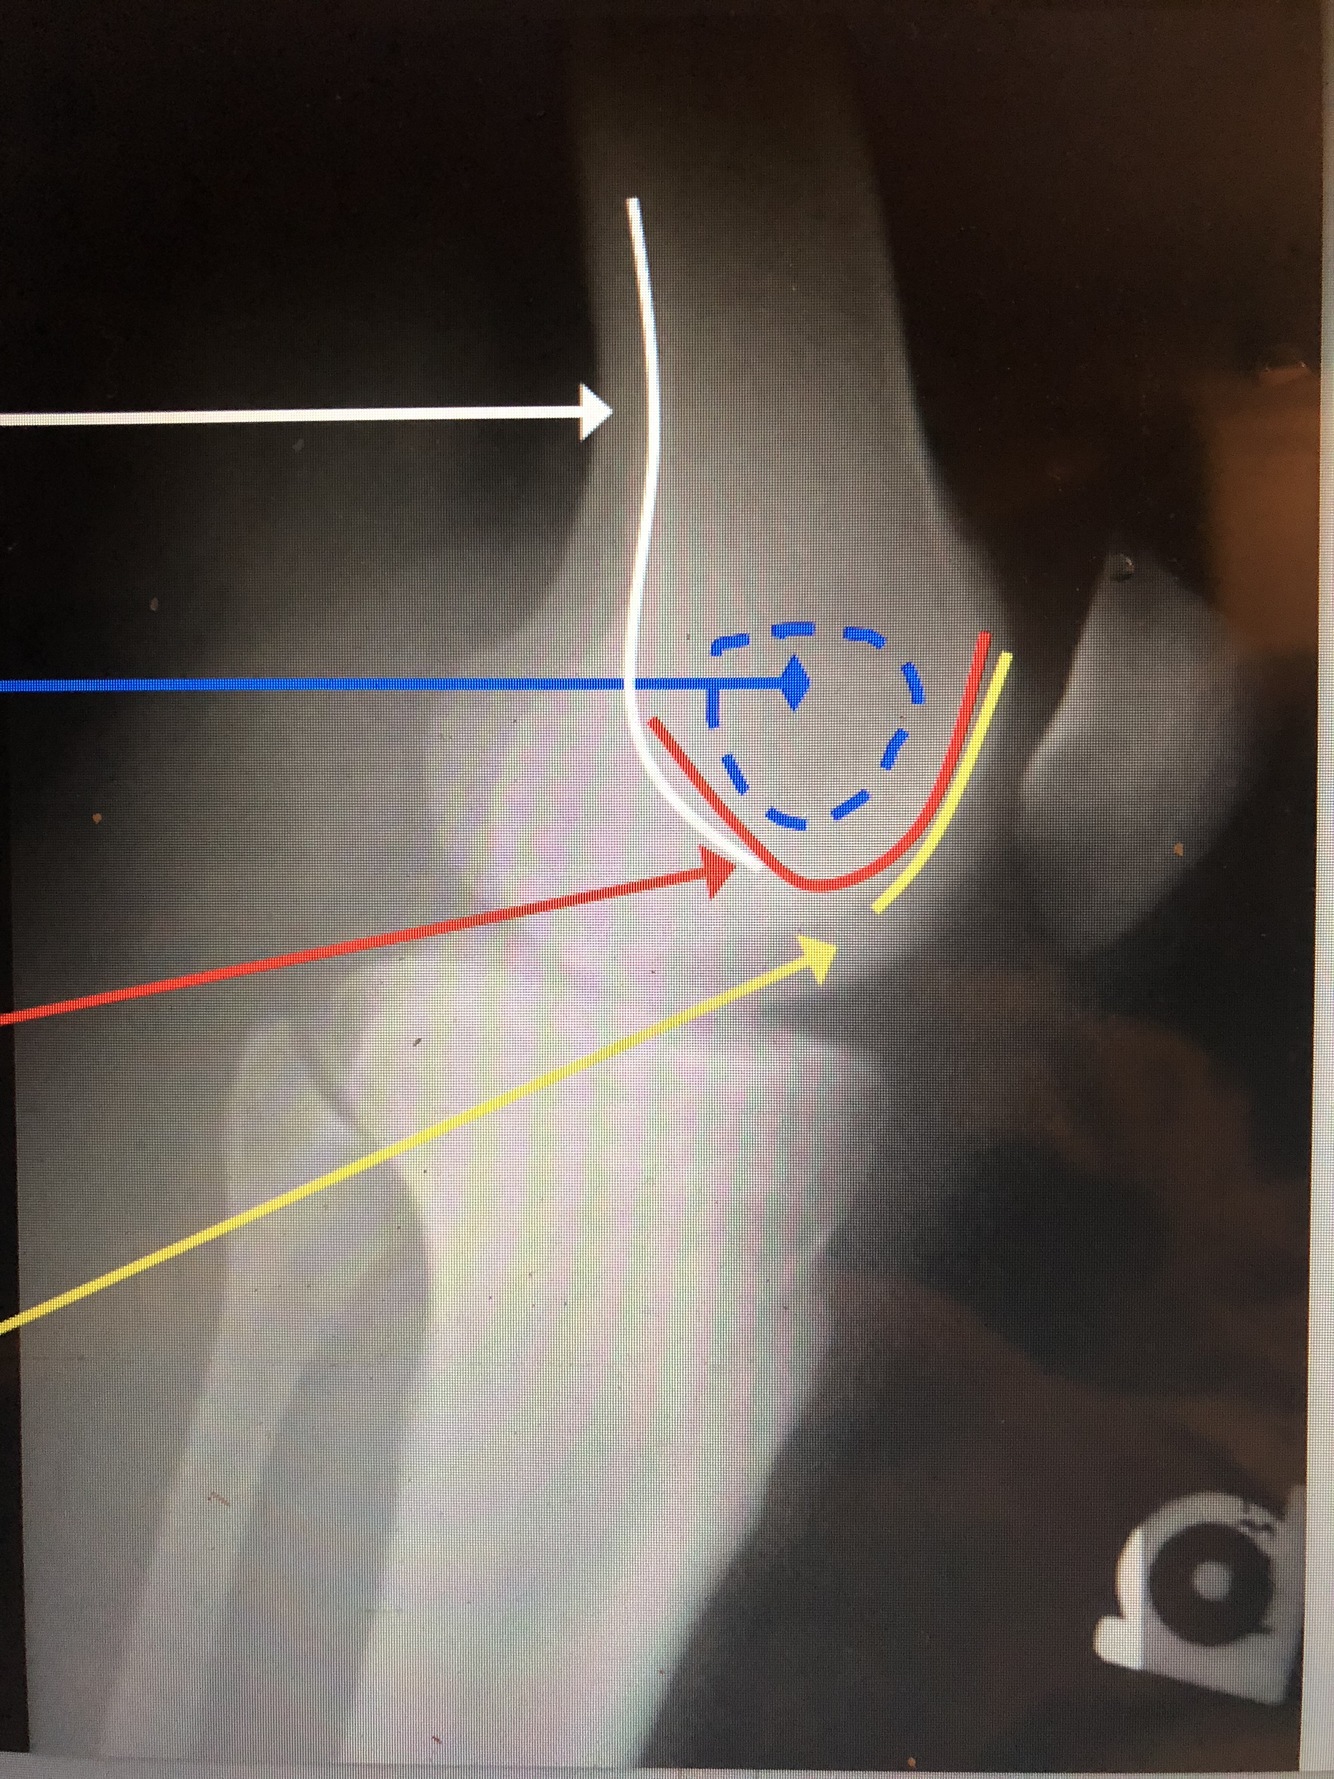

What is the white line?

Popliteal Surface of the Femur

What is the blue dotted lines?

Ludloff’s Spot – area of lucency in condyles

What is the red line?

Intercondylar Notch/Groove

What is the yellow line?

Patellar Surface of the Femur